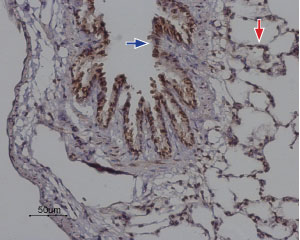

Anti-Orai2 Antibody (#ACC-061) is a highly specific antibody directed against an epitope of the mouse protein. The antibody can be used in western blot and immunohistochemistry applications. It has been designed to recognize Orai2 from human, mouse, and rat samples.